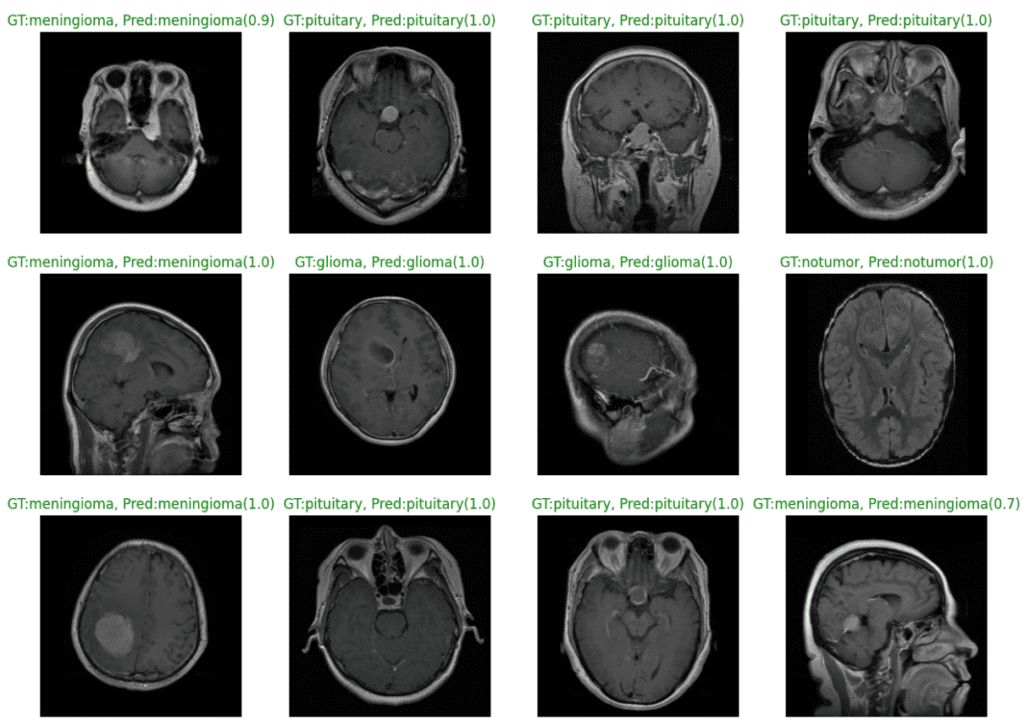

The plot below shows the model predictions from the fine-tuned EfficientNetv2 small model. We can see that the model classifies all the samples correctly with 100% confidence, barring a couple of instances.